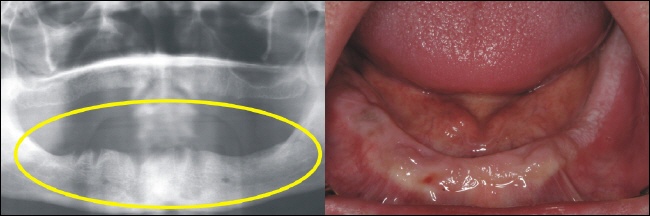

Das Bild rechts zeigt den zahnlosen Oberkiefer. Im Röntgenbild sieht dies aus wie auf dem linken Bild (gelber Kreise). |

Der zahnlose Unterkiefer rechts im Bild bietet keinen Halt mehr für eine Prothese. Links zeigt sich der zahnlose Knochenabschnitt im Röntgenbild (gelber Kreis). |